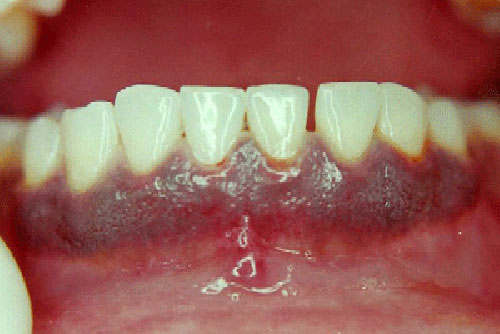

Treatment of dark/pigmented gums - Gingival depigmentation

Gingival Depigmentation